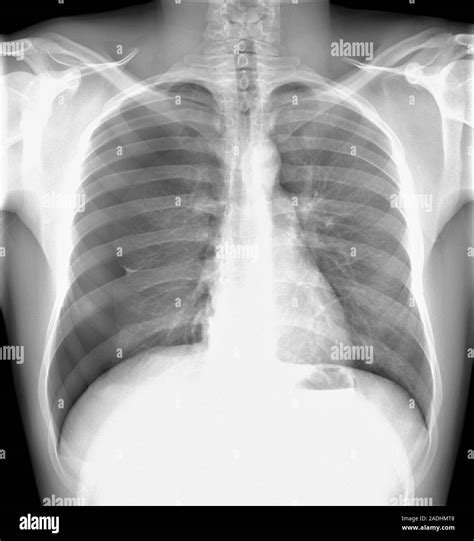

Pneumothorax is a medical condition characterized by the presence of air or gas in the pleural cavity, the space between the lungs and the chest wall. This condition can be life-threatening if not promptly diagnosed and treated. One of the most effective diagnostic tools for identifying pneumothorax is the X Ray Of Pneumothorax. This imaging technique provides a clear view of the lungs and the pleural space, allowing healthcare professionals to detect the presence of air and assess the severity of the condition.

An X Ray Of Pneumothorax is a crucial diagnostic tool for identifying and evaluating pneumothorax. The X-ray image provides a detailed view of the lungs and the pleural space, allowing radiologists to detect the presence of air and assess the extent of the condition. This information is essential for determining the appropriate course of treatment.

An X Ray Of Pneumothorax involves passing a beam of X-rays through the chest and capturing the resulting image on a film or digital detector. The X-rays are absorbed differently by various tissues in the body, creating a contrast that allows radiologists to distinguish between different structures. In the case of pneumothorax, the presence of air in the pleural space appears as a dark area on the X-ray image, contrasting with the lighter areas representing the lung tissue.